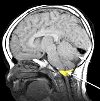

Краниовертебральная декомпрессия при аномалии Арнольда-Киари

Черепно-вертебральная декомпрессия с аномалиями Арнольда-Киари показана только в тех случаях, когда патология проявляется прогрессирующими неврологическими симптомами в виде мозжечковой координации движений, пареза, глотания и нарушения языка вследствие сдавления мозжечка и продолговатого мозга. в месте соединения черепа с позвоночником (внутричерепной мозг и продолговатый мозг удлиняются в месте соединения черепа со спинным мозгом). Сущность краниовертебральной декомпрессии состоит в резекции нижней части затылочной кости размером около 2,5 х 2 см и удалении задней дуги первого шейного позвонка, что приводит к устранению сдавления структур головного мозга и к устранению dell idrocepalo.